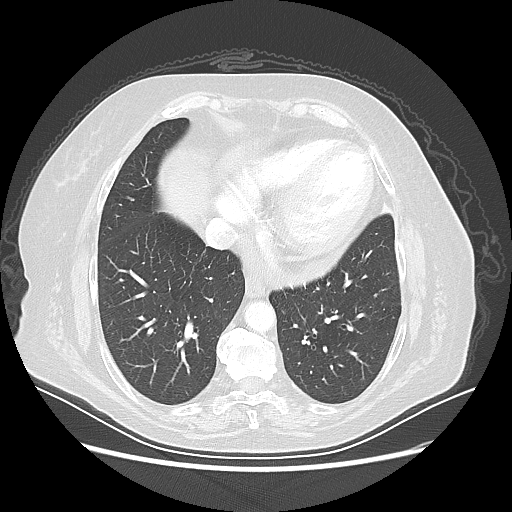

Generated VENOUS CT scan (A→B translation)

Lung window (WL -600, WW 1500 β†’ Low βˆ’1350, High +150)